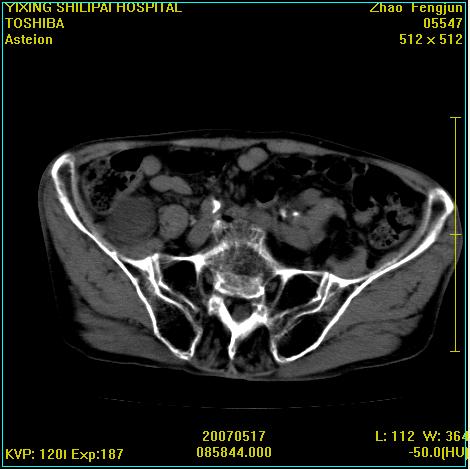

考虑:1、左侧腰大肌囊实性占位性病变(囊性神经根鞘瘤?);

2、右侧兰尾区囊性占位性病变(兰尾囊肿?囊腺癌?类癌?)

以下是引用xiaoniu在2007-5-26 10:45:00的发言:[br]腰大肌的病变应该没有问题,增强扫描还有轻度强化及细小血管影入内,应该排除脓肿,考虑占位性病变,腰大肌的占位多考虑:神经源性肿瘤。另外腹主动脉下端有真假腔的强化,考虑:主动脉夹层。[br][br][本贴已被 xiaoniu 于 2007-5-26 10:46:39 修改过]

以下是引用老爱克斯新网客在2007-5-26 18:26:00的发言:[br]1左下腹囊实性占位肿块,增强后不均匀强化,位于脊柱旁,椎体骨质无破坏软组织无肿胀,考虑神经源肿瘤神经鞘瘤可能大,2右下腹囊性占位性病变,增强后囊壁强化,考虑阑尾囊肿或囊腺瘤,